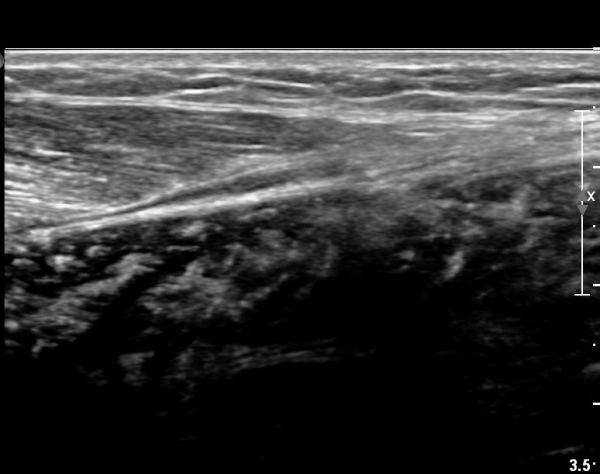

[¹ß¸ñ] simultaneosus tear of GCM and achiles tendon

pain on rt. leg( du: 1 day)

abrupt leg pain developed during foot volleyball

he walk with severe limping with no weight bearing on rt. leg. on examination, there is local tendernes at GCM and achiles tendon, severe pain with ankle dorsiflexion.

ÃÊÀ½ÆÄ °Ë»ç

rec) short leg splint with crutch gait. he refused splint, then visit other hospital and took operation.